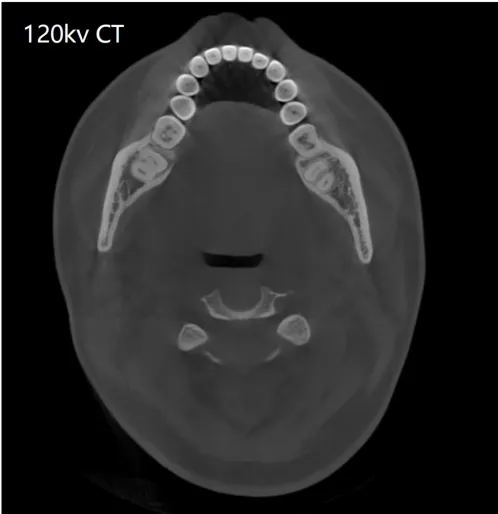

可靠的诊断始于清晰的影像。神农·云CT全新升级双能技术,能从物理层面有效识别并分离由金属植入物产生的伪影,显著降低其对周围关键解剖结构的干扰。

这项技术为种植规划提供了干净、可靠的影像基础,使医生能够清晰地辨识牙槽骨形态、骨小梁结构、神经管走向以及邻牙关系,将诊断依据从基础的“看得见”提升至精准的“看得准”,为后续每一步决策筑牢安全基石。